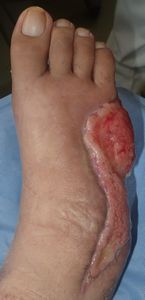

42歳男。

2016年2月中旬から発熱が続き,近くの〇〇病院内科に通院していたが,右第5趾の色が黒くなり,2月29日に△△院に救急搬送された。ここで初めて糖尿病指摘(血糖450,HbA1c 14)の指摘を受けた(内服薬で血糖コントロール中)。

入院後,同院整形外科で直ちに第5趾切断術。その後,2度追加手術(デブリードマンらしい)。3月7日よりVAC療法。現在はプロスタンディン軟膏とガーゼで治療。治癒しないため,当科紹介となった。

4月27日,当科受診。ズイコウパッドで治療。5月25日,関西の実家に戻ることになり,用事があって東京に来た際に受診していただくこととした。